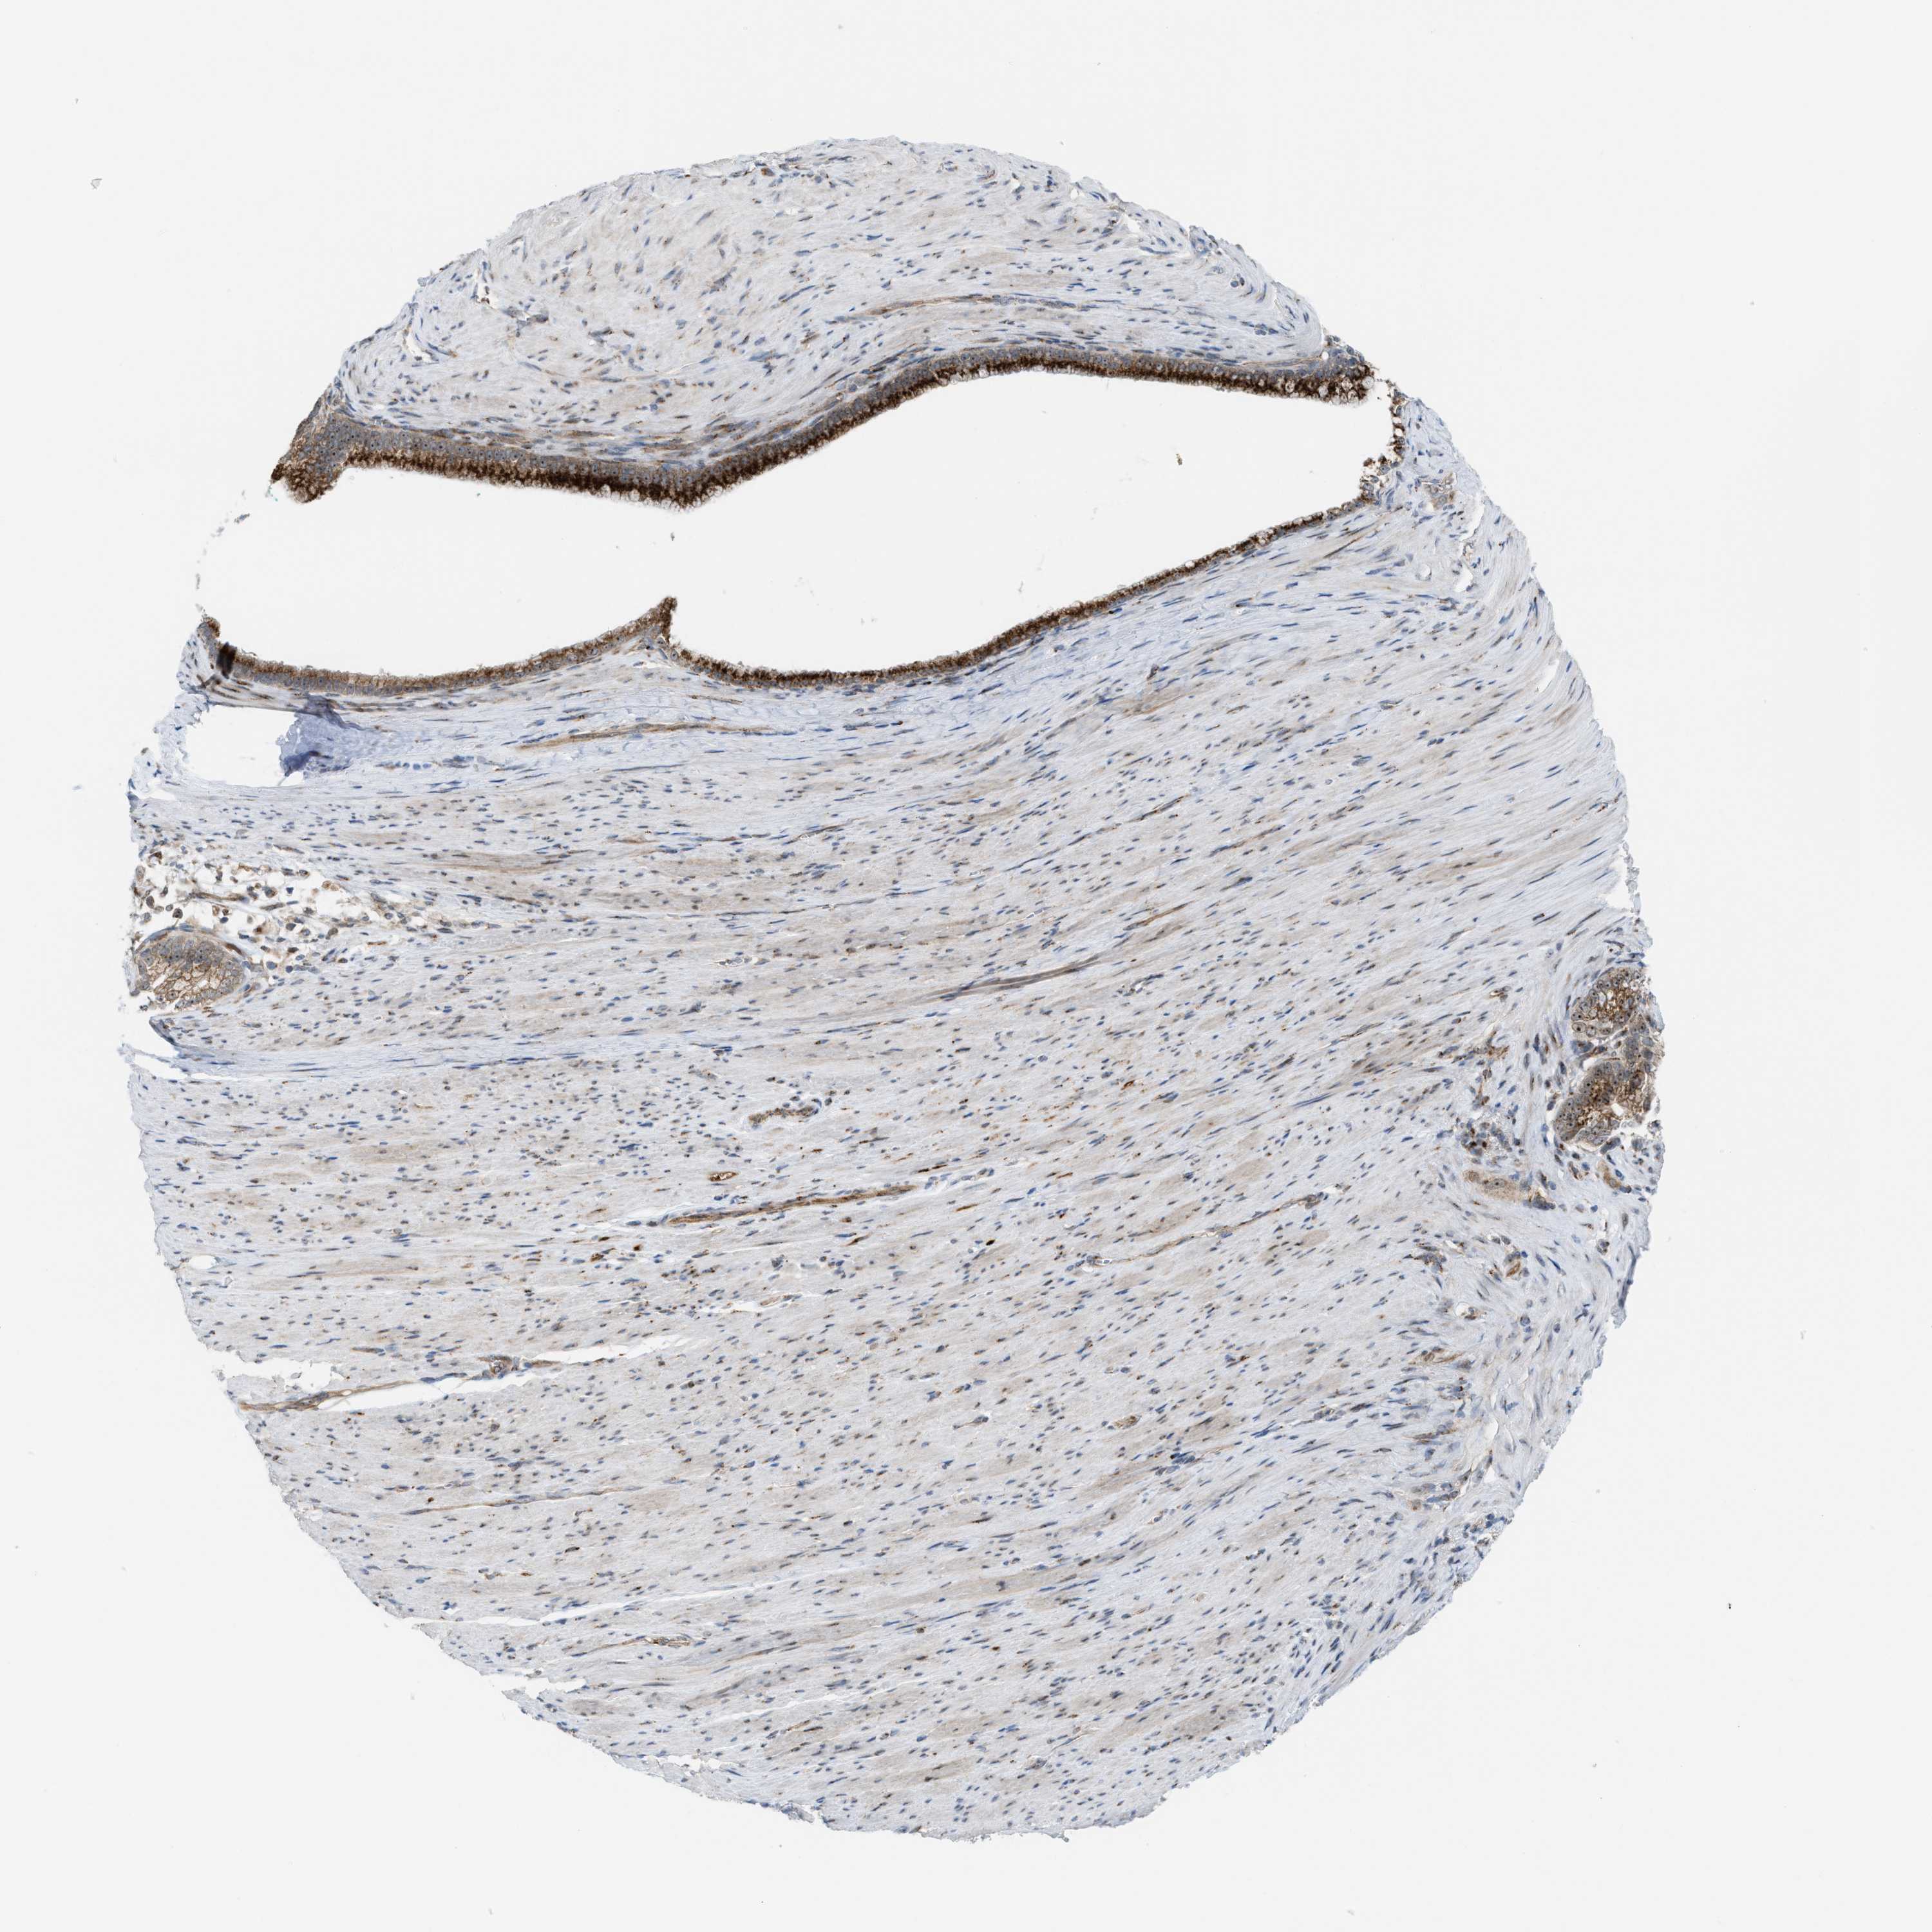

PANCREATIC CANCER - Protein expressioni

A mouse-over function shows sample information and annotation data. Click on an image to view it in a full screen mode. Samples can be filtered based on level of antibody staining by selecting one or several of the following categories: high, medium, low and not detected. The assay and annotation is described here.

Note that samples used for immunohistochemistry by the Human Protein Atlas do not correspond to samples in the TCGA dataset.

Antibody stainingi

Antibody staining in the annotated cell types in the current human tissue is reported as not detected, low, medium, or high, based on conventional immunohistochemistry profiling in selected tissues. This score is based on the combination of the staining intensity and fraction of stained cells.

Each image is clickable and will lead to virtual microscopy that enables deeper exploration of all samples and also displays staining intensity scores, fraction scores and subcellular localization as well as patient and tissue information for each sample.

Antibody HPA021374

Antibody HPA023161

Antibody HPA024631

Staining

High

Medium

Low

Not detected

Intensity

Strong

Moderate

Weak

Negative

Quantity

>75%

75%-25%

<25%

None

Location

Nuclear

Cytoplasmic/membranous

Cytoplasmic/membranous,nuclear

Adenocarcinoma, NOS